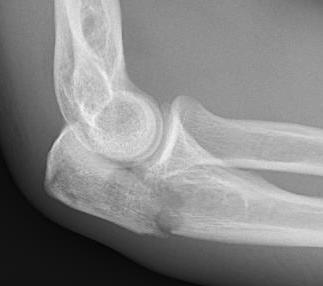

Mayo Classification

A: Non comminuted

B: Comminuted

| Type I | Type II | Type III |

|---|---|---|

| Minimally displaced | Displaced | Trans-olecranon fracture dislocation |

| 10% | 85% | 5% |